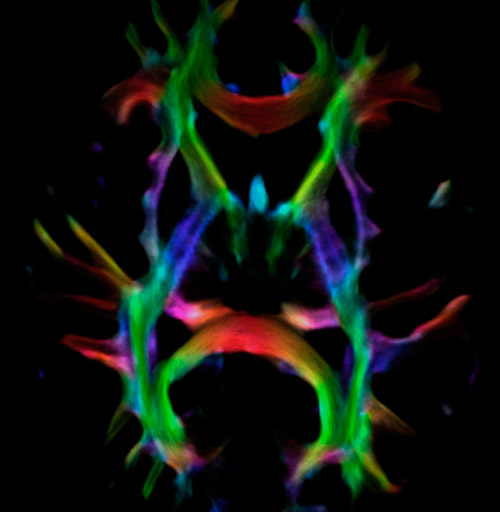

Fiber tracking from the left and right hippocampi to the fornix.

Fiber tracking from the left and right hippocampi to the fornix (green), and the corticospinal track based on a seed region of the posterior limb of the internal capsule.